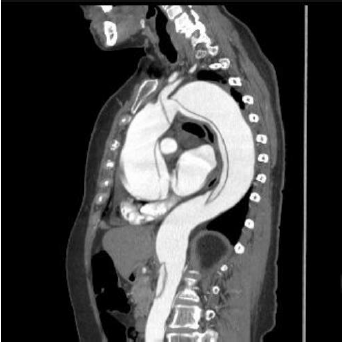

Das condições a seguir, assinale a que não está geralmente associada à emergência cardiovascular visualizada na imagem.